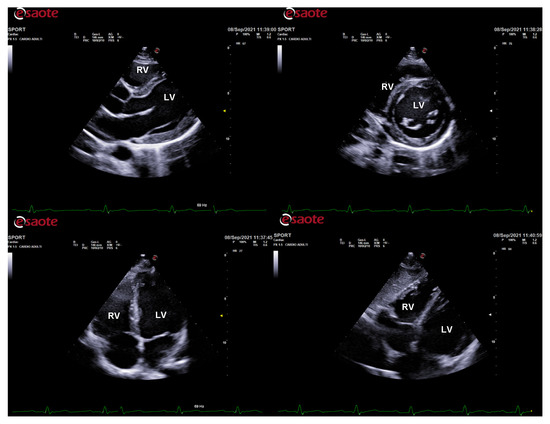

Myocardial work (MW) is a novel, less load-dependent ultrasonographic index of LV contractile function, which corrects STE-derived parameters for afterload, by using systolic blood pressure [55]. In different physiologic and pathologic conditions, an increased afterload may lead to strain impairment, with preserved or increased MW indices. This may be important for athletes with variable blood pressure and loading conditions from exam to exam and in different phases of the training program (Figure 2).

Figure 2.

Myocardial work analysis in a power athlete (bodybuilder). On the left, left ventricular pressure–strain loop, showing the relationship between left ventricular systolic pressure and global longitudinal strain. On the right, the 17-segment bull’s-eye representation of myocardial work efficiency, showing homogeneous areas of high efficiency coded in green.

ColorDoppler flow mapping is an advanced echocardiographic tool that evaluates LV function through the analysis of intracardiac flows [56]. LV vortex flow study may provide new insights into the characterization of athlete’s heart properties and its differences with normal subjects and patients with cardiomyopathies (Figure 3).

Figure 3.

HyperDoppler flow analysis in an endurance athlete. On the left, the flow velocity vector map shows the blood flow that circulates towards the direction of the left ventricular outflow tract. On the right, the circulation parametric map brings to light the formation of a pair of vortices immediately below the aortic valve.